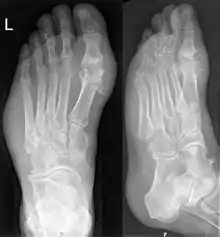

Подагру можна діагностувати та лікувати без подальшого проведення аналізів у деяких людей з гіперурікемією та класичною подагрою. Слід провести аналіз синовіальної рідини, якщо є сумніви щодо діагнозу.[4] Незважаючи на те, що рентгенографія може допомогти ідентифікувати хронічну подагру, він майже не допомагає у разі гострих нападів.[9]